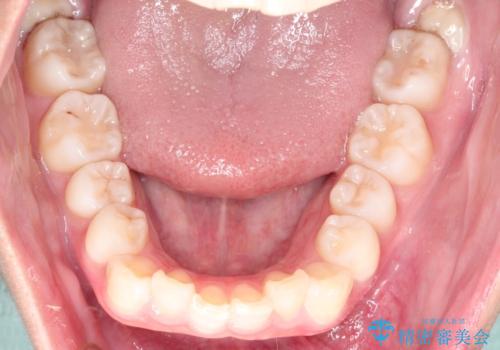

- 出っ歯を主訴に来院されました。

下の歯並びに対して、上の歯が全体的に前方に位置している状態でした。

治療について

抜歯をすることでしっかり前歯を後方に移動させて、引っ込めることができました。